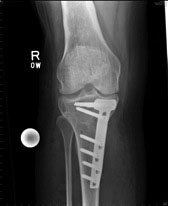

As things progress patients often develop severe night pain and when you are getting to that stage most people want to get something done about it. If lifestyle modification hasn’t worked, you have tried the anti-inflammatories, you have tried to lose weight, you’ve stopped doing impact exercises, you’ve tried your glucosamine, you’ve even gone to the trouble of buying an offloader brace and tried to offload the painful knee compartment (and they don’t tend to work very well with the braces – some people get on with them but most people struggle), then the next step for you is going to be surgery. The surgery for purely varus or valgus osteoarthritis is either an osteotomy (left image) or a knee replacement (partial knee replacement or a complete knee replacement) (right image).